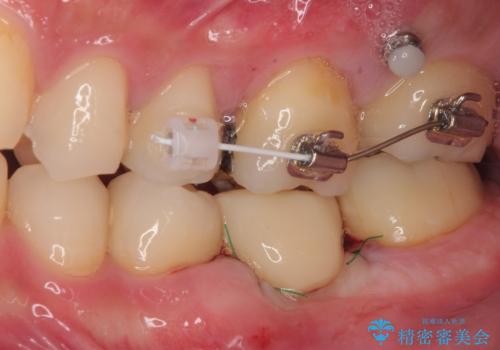

- 左下欠損部のインプラント治療を希望して来院された患者様です。

左下の欠損部を長期間欠損を放置していたことで、咬み合う上の奥歯が動いてしまっている状態でした。

インプラント部は埋入とともに仮歯を装着し、同時に上顎奥歯の部分矯正を開始することとしました。